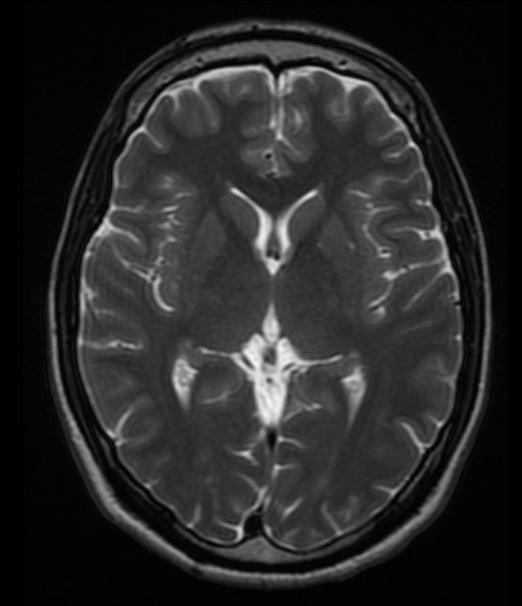

不同的组织内的氢原子核,其T2弛豫时间也不同。比如,脑组织的T2弛豫时间要短于脑脊液。基于T2弛豫生成的脑图像称为T2加权图像(T1 weighted image)。

T2图像无法区分灰质白质,脑脊液呈亮白色